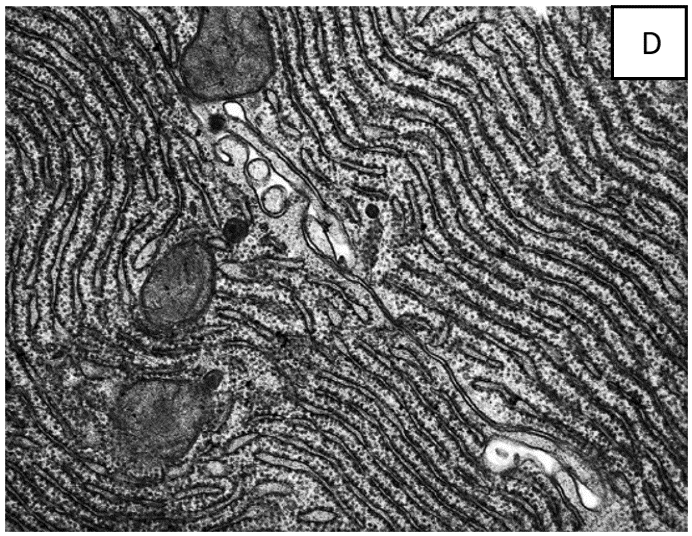

האמונה היא שאברון זה נמצא בכל תאי הצמחים ובעלי החיים כרשת תלת ממדית או כמערכות של שקים שטוחים, או בועיות, החודרות דרך חלק או כל נפח הציטופלסמה. נראה גם שיש לו שתי שכבות עם רווח ביניהן, כמו במקרה של "קרום התא". ראו מיקרוגרפים אלקטרונים D ו-E.

הבעיה הגדולה ביותר של הילמן וסארטורי עם ההסבר לעיל היא שבכל מיקרוגרף אלקטרונים המסופק כראיה למיון בתאים, הר"א נראית תמיד רק באותו מישור כמו התמונה, בחתך רוחבי.

הבעיה עם זה היא, שאם הר"א היתה רשת או סדרה של שקיות שטוחות, אפשר היה לצפות לראות אותה בחתך מכל מיני כיוונים ולא רק מאחד. אם [בעת החיתוך] הר"א נמצאת במנח אקראי בתוך התא, הסכין היה צריך לחתוך אותה בצורה אקראית. בנוסף, בסדרה של חתכים כאלה הר"א היתה צריכה להראות חתוכה מסדרה של כיוונים.

במילים אחרות, אם הר"א היא מעין רשת העשויה קרום בדומה לקרום התא, מדוע אנו רואים תמיד רק חתך מכיוון אחד שלו בתאים? איפה התמונות של חתכים מכל הכיוונים השונים שהיינו מצפים לראות? זה די בלתי אפשרי להעלות על הדעת אובייקט תלת-מימדי, אשר נראה תמיד אותו הדבר בשני ממדים, כאשר חותכים אותו מכיוונים שונים.